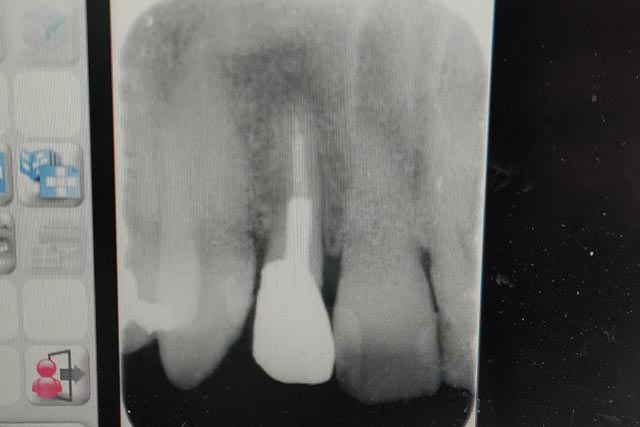

ターゲットの差し歯のレントゲン写真を撮影し、今後の医療方針の確認。

![]() |

| ・対象の差し歯の最新レントゲン写真 |

歯の根元に黒い影が写っていて、これも化膿している可能性があるので、ただ単に歯を抜くだけでなくこの部分もしっかりと取り去りたい。